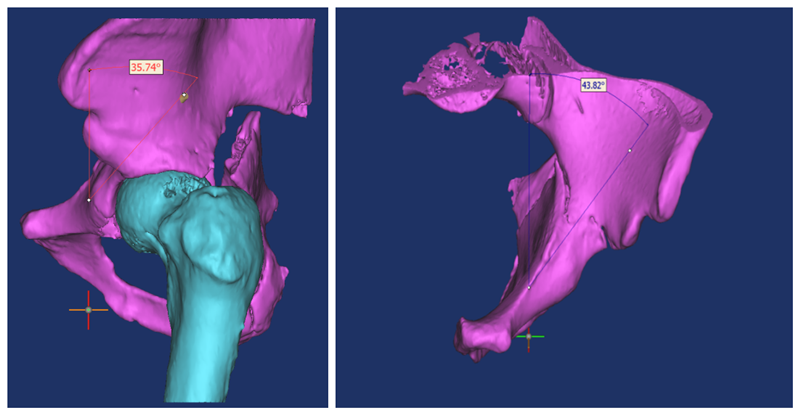

我们应用软件自动建立虚拟骨盆三维仿真模型,应用相关软件功能模块建立虚拟圆柱体替代拉力螺钉,将虚拟圆柱体置入髋臼前柱骨质内,逐渐增大虚拟圆柱体的直径直至髋臼前柱骨质边缘,在三维层面中记录虚拟圆柱体的直径及长度,并测量入钉点与相关髋臼解剖结构的距离,测量虚拟圆柱体的入钉角度及螺钉在骨盆正位、入口位与骨盆正中线的夹角。在得到精准的螺钉入点、长度、角度等测量值后,为术中置钉提供了较为重要的参考价值。

(术前模拟规划前柱通道螺钉入点与角度)

(术中角度验证)